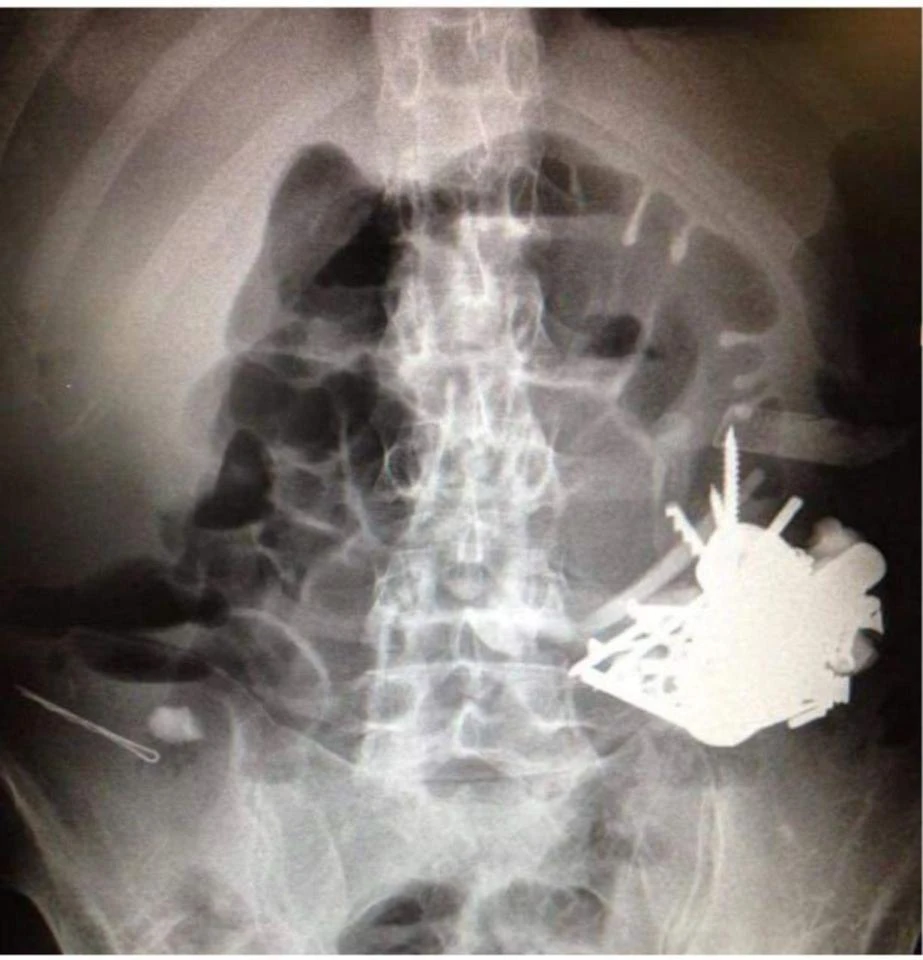

Hình ảnh chụp khối dị vật trong bao tử bệnh nhân.